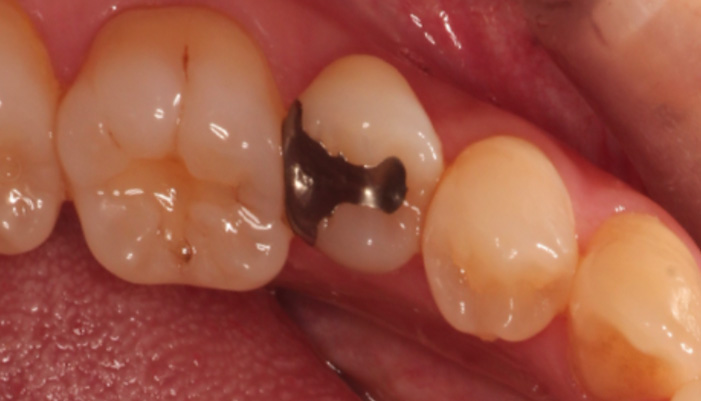

治療中

拡大視野下でむし歯の感染部位を丁寧に確認しながら正確に除去し、歯髄の状態を評価しました。その結果、神経を残せる可能性があると判断し、MTAを用いた歯髄温存療法を選択しました。神経を残すことは、歯の寿命を守ることにもつながります。

| 主訴 | 甘いものや冷たいものがしみる |

|---|---|

| 治療期間 | 1〜3回 |

| 治療費 | ¥33,000 |

| 治療内容 | 深い虫歯に対して歯髄を保護する処置を行い、神経を残す治療を行いました。 |

| 治療のリスク | 虫歯の進行度によっては将来的に神経の治療が必要になる場合があります。 |